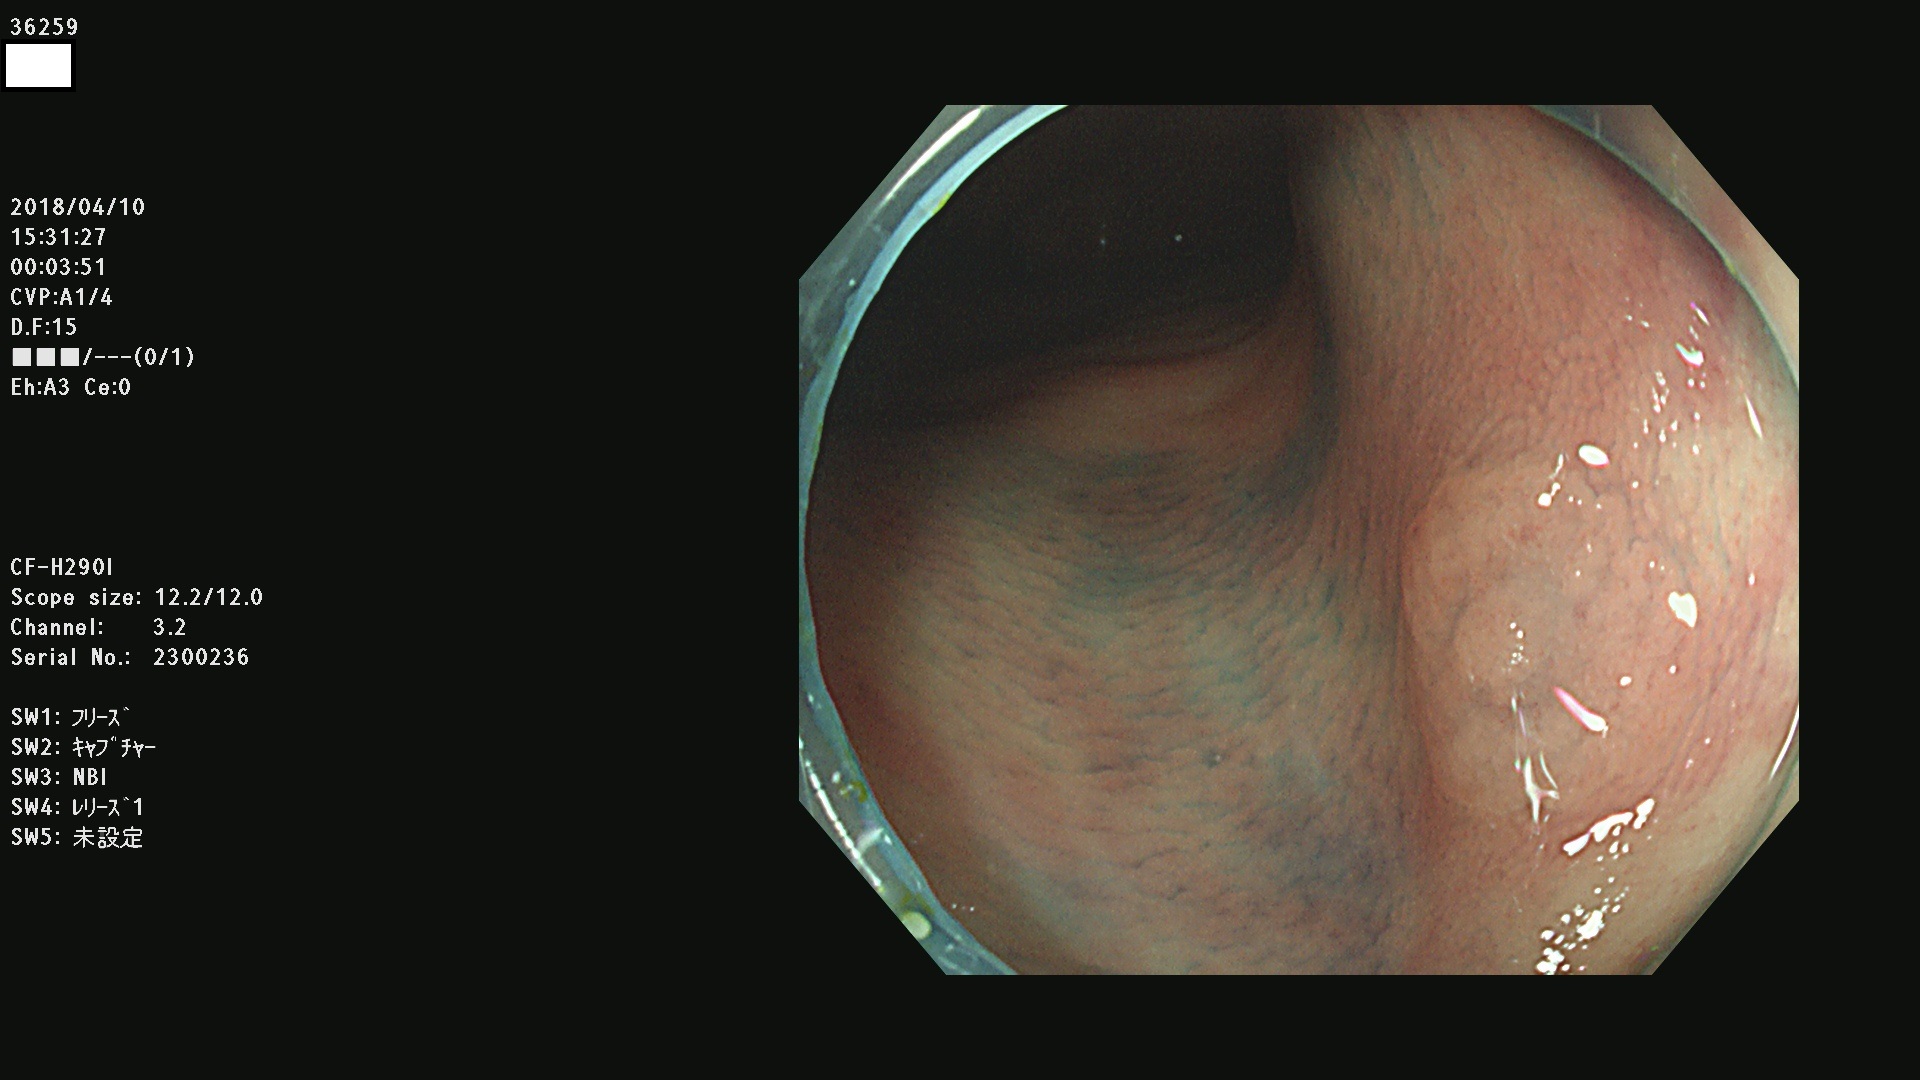

36201 36202 36203 36205 36207 36209 36210 36212 36213 36214 36215 36217 36220 36221 36222 36224 36225 36226 36227 36229 36230 36231 36232 36235 36236 36238 36240 36243 36244 36246 36247(SSAPのみ。SPS) 36248 36249 36251 36252 36253 36254 36255 36256 36257 36258 36259 36261 36262 36264 36265 36267 36269 36270 36272 36274 36275 36276 36279 36280 36281 36283 36285 36288 36289 36291 36292 36295 36296 36297 36299

発見困難で危険性の高い平坦型病変(上記100名より抽出)